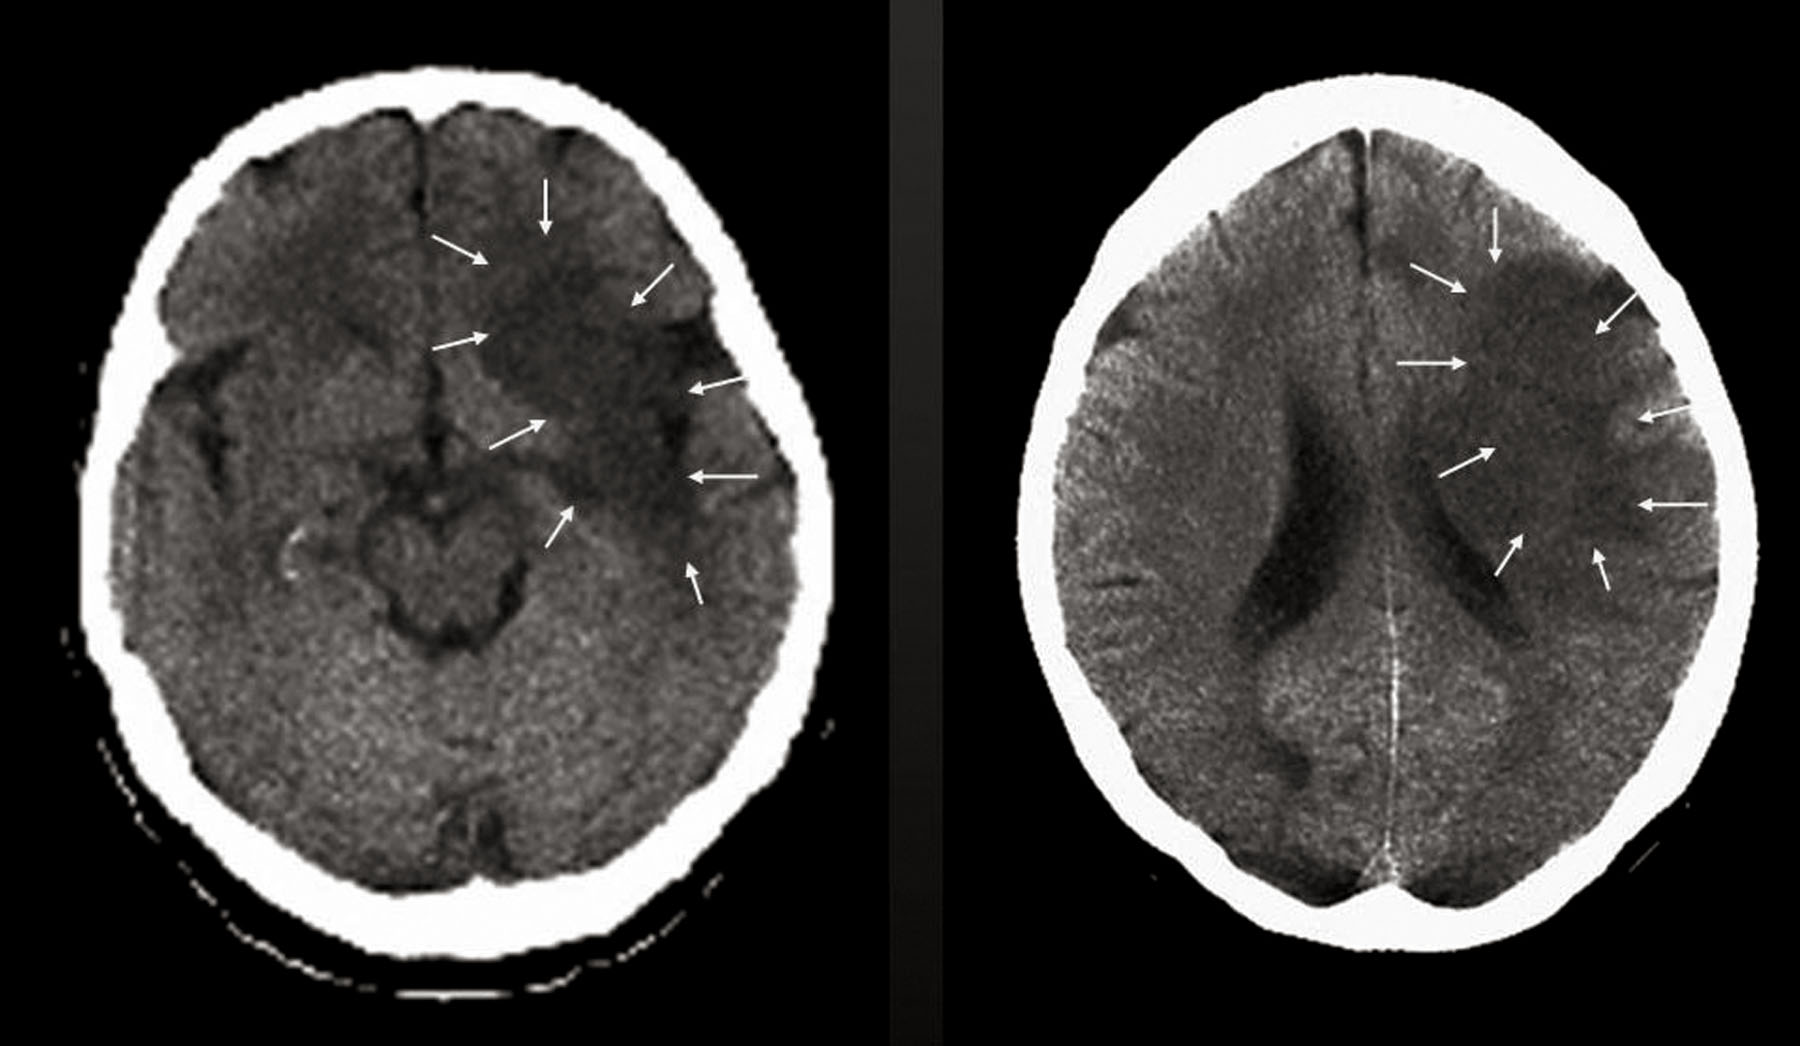

Foto: Infarto cerebral © JMJH